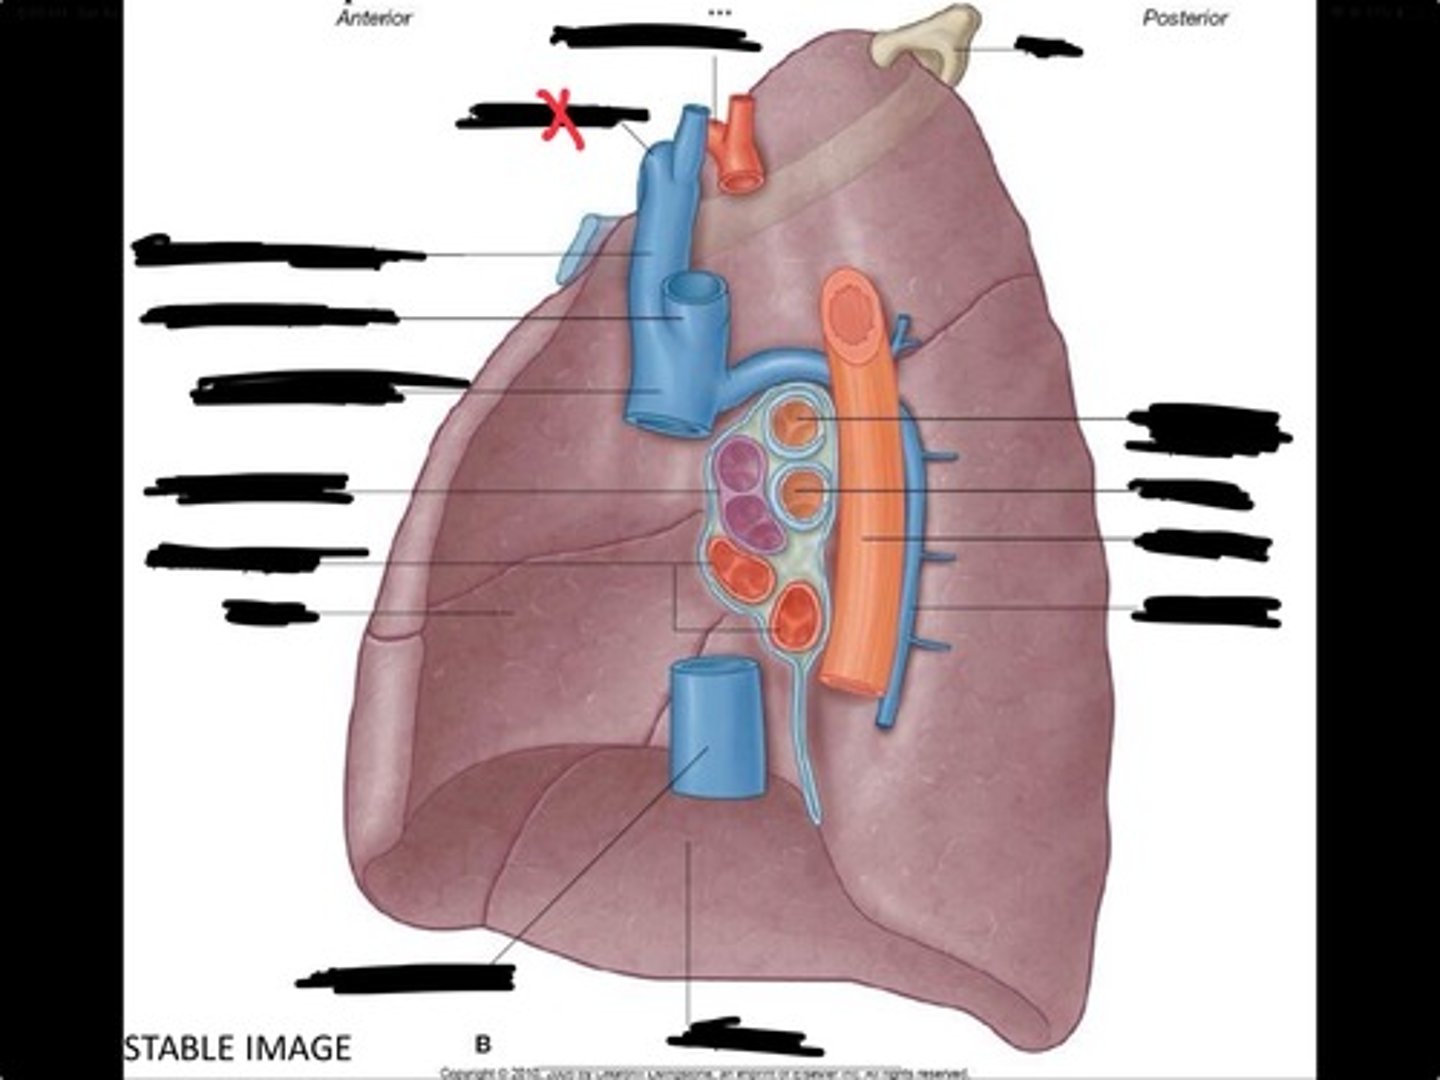

Rib 1

Pulmonary artery

Bronchus to superior lobe

Pulmonary veins